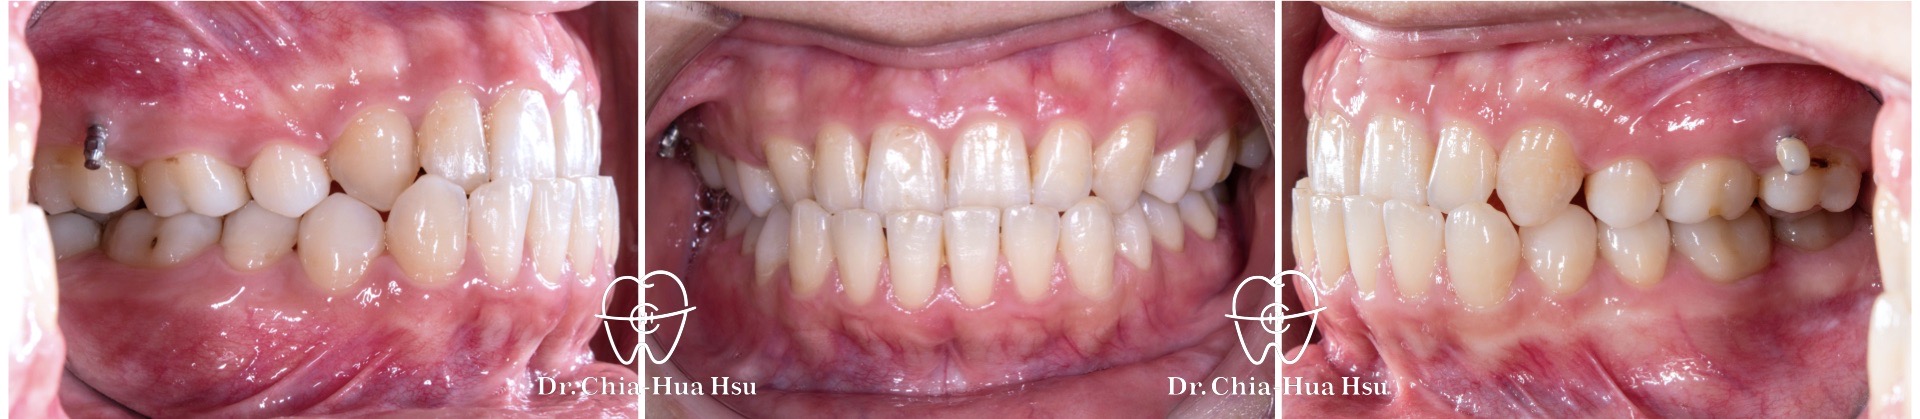

治療前

治療後